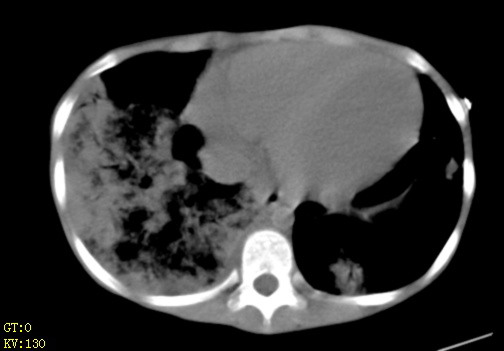

女,12岁,气促、咳嗽2天,3个月前查胸片示:两肺感染,急诊入院查ct,血常规等未检查。

1、左心房、左心室增大,考虑左心衰, 2、肺水肿合并感染 3、双侧胸腔积液

双肺中下野不规则片絮状阴影,中外带明显,双侧胸腔少量积液,心影增大,心腔密度减低,隆突下及左侧气管旁见钙化淋巴结影,考虑双肺感染、心衰;建议结合临床除外h1n1并急性心衰,先心不能排除。

两肺多发片絮状模糊影,以下肺外带居多,内见支气管气像,纵膈窗未减影,两侧胸腔积液,心影增大,结合心超,支持重症肺炎,非常时期,甲型h1n1流感不排除。